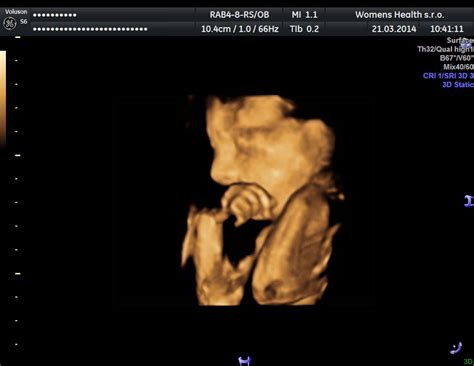

Prirodzené pre dieťa je cmúľanie prštekov, ktoré sa prejavuje už v prenatálnom období. Na záberoch z ultrazvuku je bežne vidieť bábätko s palčekom v ústach ešte v brušku. Okrem toho sa bábätko zvykne prisať na čokoľvek - prsník, prst či nos matky pri maznaní, i na okolité predmety. Tento reflex sa prejavuje zhruba do pol roka.